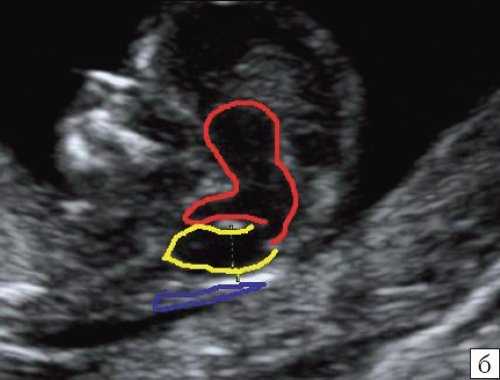

б) Вид "осьминожки":

- красный цвет - диэнцефалон (таламус), со стволом мозга (верхняя ножка) и IV желудочком (нижняя ножка);

- желтый цвет - большая цистерна головного мозга;

- синий цвет - воротниковое пространство.

Так как речь идет о сроках первого скрининга, т.е. раннего осмотра, новый ультразвуковой маркер мы назвали "осьминожкой" (рис. 3).

а) Стрелками указана голова "осьминожки" - диэнцефалон (таламус).

б) Красный цвет - диэнцефалон (таламус), со стволом мозга (верхняя ножка) и IV желудочком (нижняя ножка); желтый цвет - большая цистерна головного мозга; синий цвет - воротниковое пространство.

Как сказано выше, имеет значение и измерение ножек "осьминожки", так среднее значение диаметра нижней ножки, т.е. IV желудочка в зависимости от КТР в срок 11-14 недель варьирует от 1,5 до 2,5 мм (рис. 4).

Рис. 4. Измерение и взаимоотношение ножек "осьминожки" - ствола мозга и IV желудочка у плода, беременность 12 недель.

Измерение ножек "осьминожки".

Красный цвет - диэнцефалон (таламус), со стволом мозга (верхняя ножка) и IV желудочком (нижняя ножка); желтый цвет - большая цистерна головного мозга; синий цвет - воротниковое пространство.